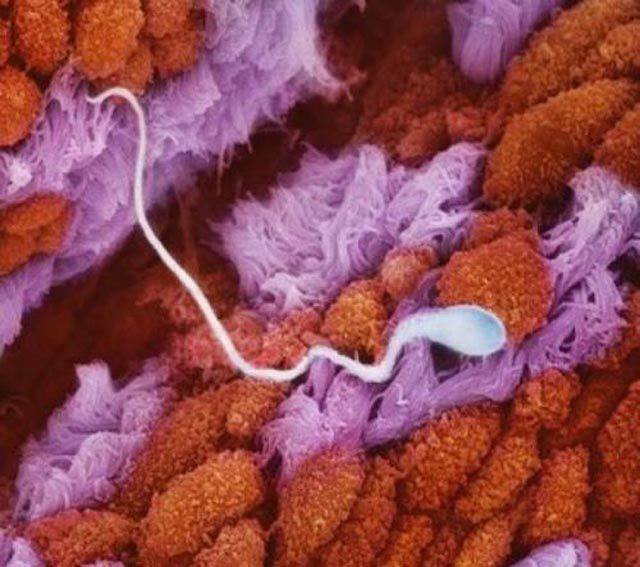

1.精子還在輸卵管裡遊動的模樣。

2.這個外表看起來就像是花瓣一樣的東西, 就是女性的輸卵管。